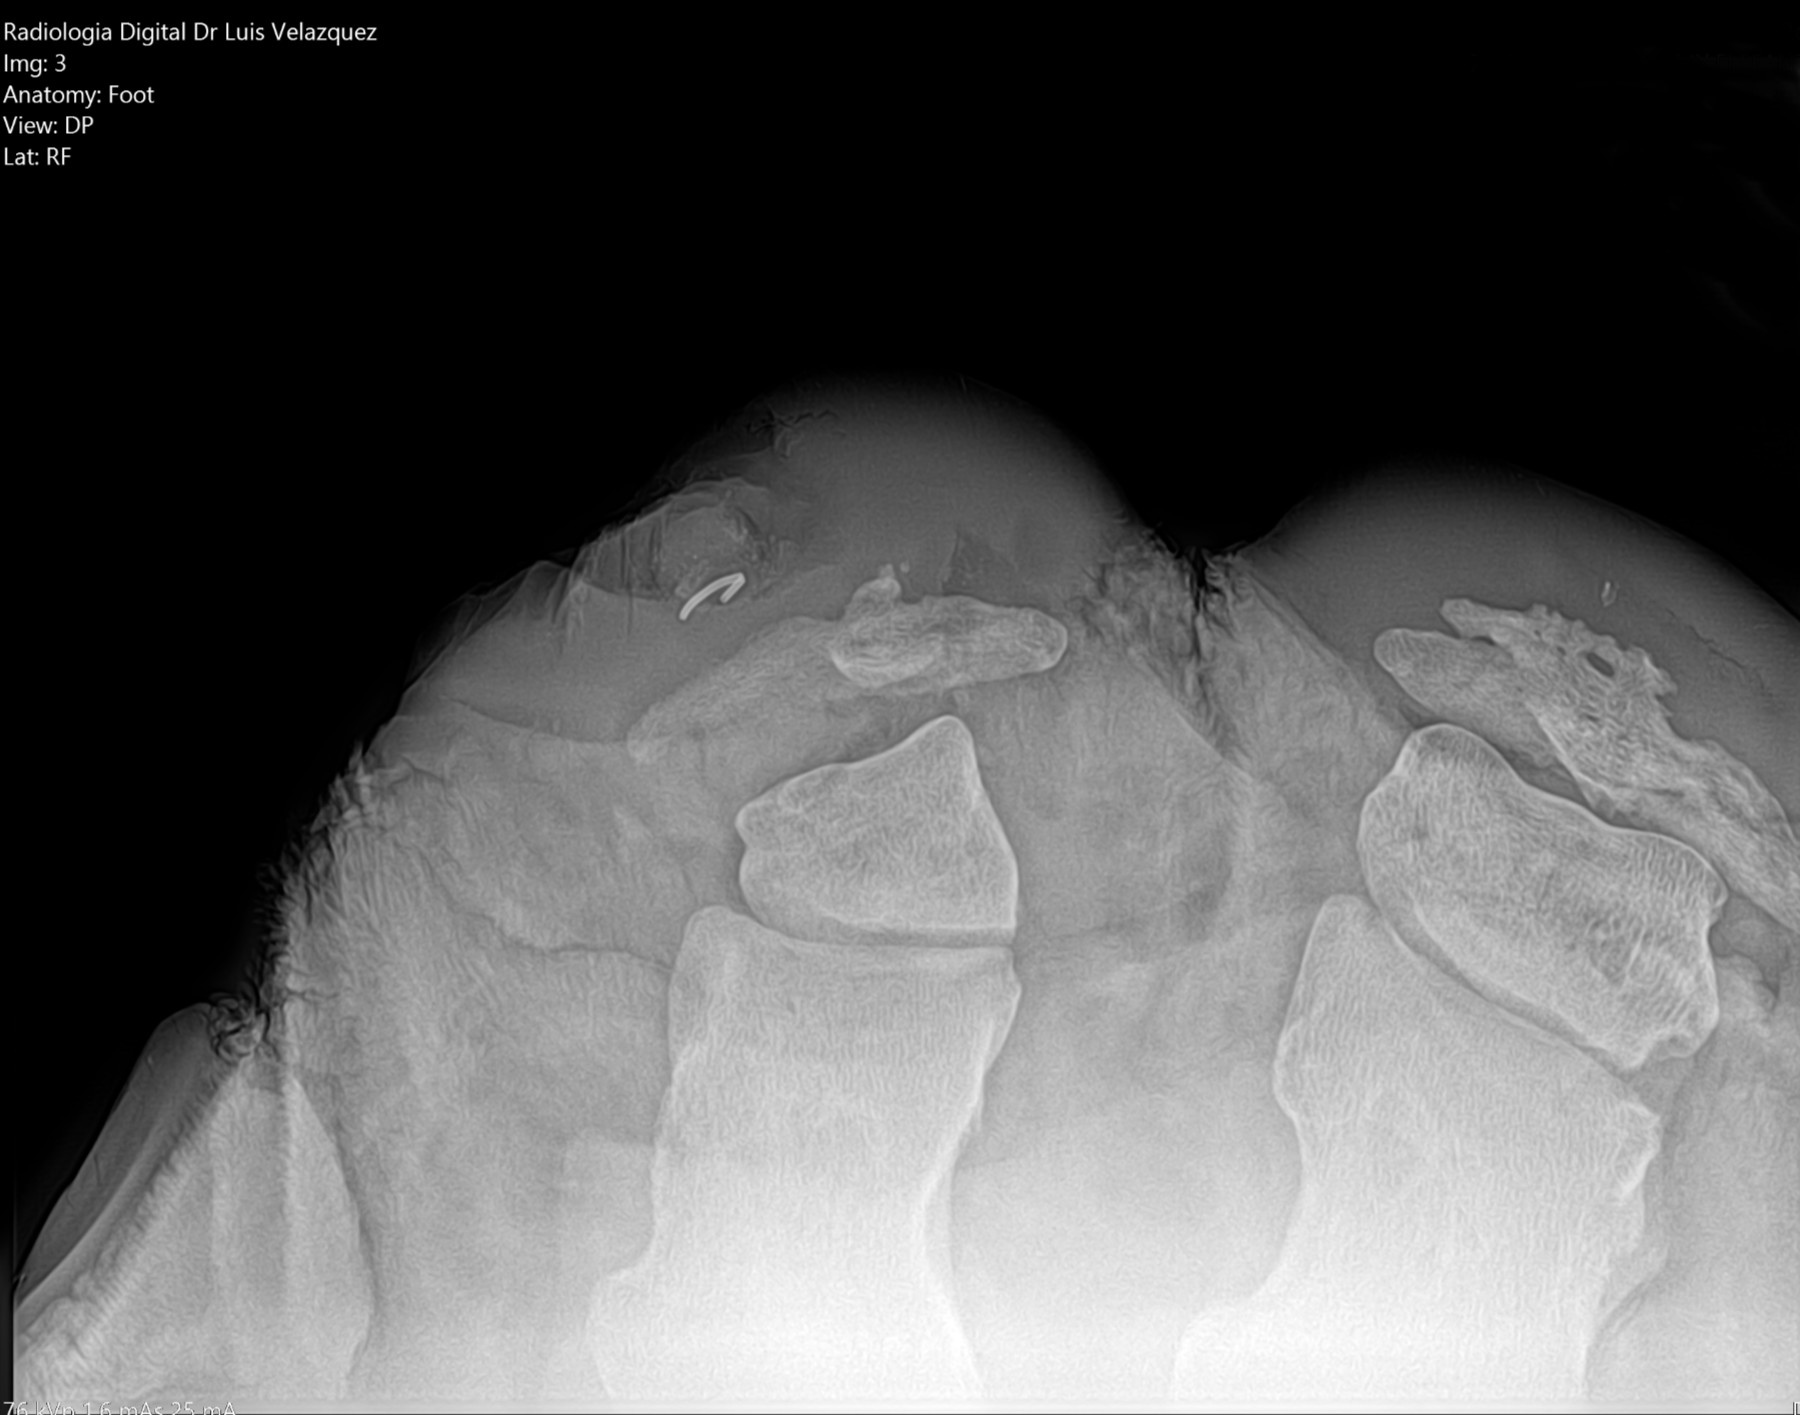

Radiología Digital como Herramienta Complementaria en el Dictamen de Bienes Muebles

Desde el descubrimiento de los rayos “X” y las placas radiográficas por Wilhelm Conrad Roentgen y su posterior difusión a través de la Asociación Físico médica de Wurzburg el 28 de diciembre de 1895, que fue la primera asociación que habló de los nuevos rayos que podían penetrar el cuerpo y fotografiar los huesos, ha habido muchos cambios tanto en la forma de obtener, procesar e incluso en la forma de visualizar, manejar y almacenar las placas radiográficas.